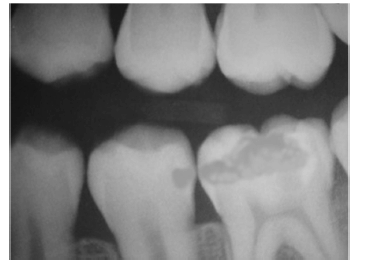

Determinada paciente de 34 anos de idade, normossistêmica, queixou-se de dor após estímulo (doce e gelado) na região de quarto sextante. Ao exame clínico, observou-se cárie oclusal no dente 36, com esmalte branco-acinzentado, opaco na direção da face mesial. A imagem radiográfica revelou a situação a seguir.

Com base nesse caso clínico e na imagem radiográfica, e considerando os conhecimentos odontológicos a eles relacionados, julgue os itens a seguir.